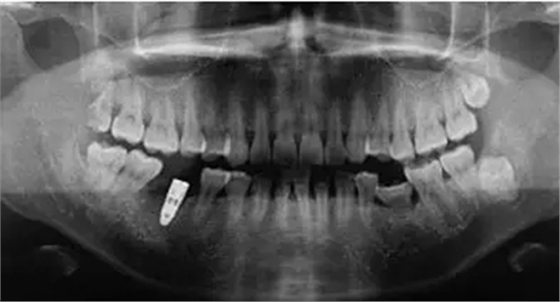

制作放射模板;制備PRF(圖2);微創(chuàng)拔除46后植入PRF(圖3)。3個月后CBCT分析骨質;行46種植牙修復術(圖4)。種植術后曲面體層片見圖5。病例2應用骨粉膠原塞牙槽位點保存后一例基本情況患者男性,47歲。主訴:右下后牙折裂半月。

圖5 種植術后曲面體層片